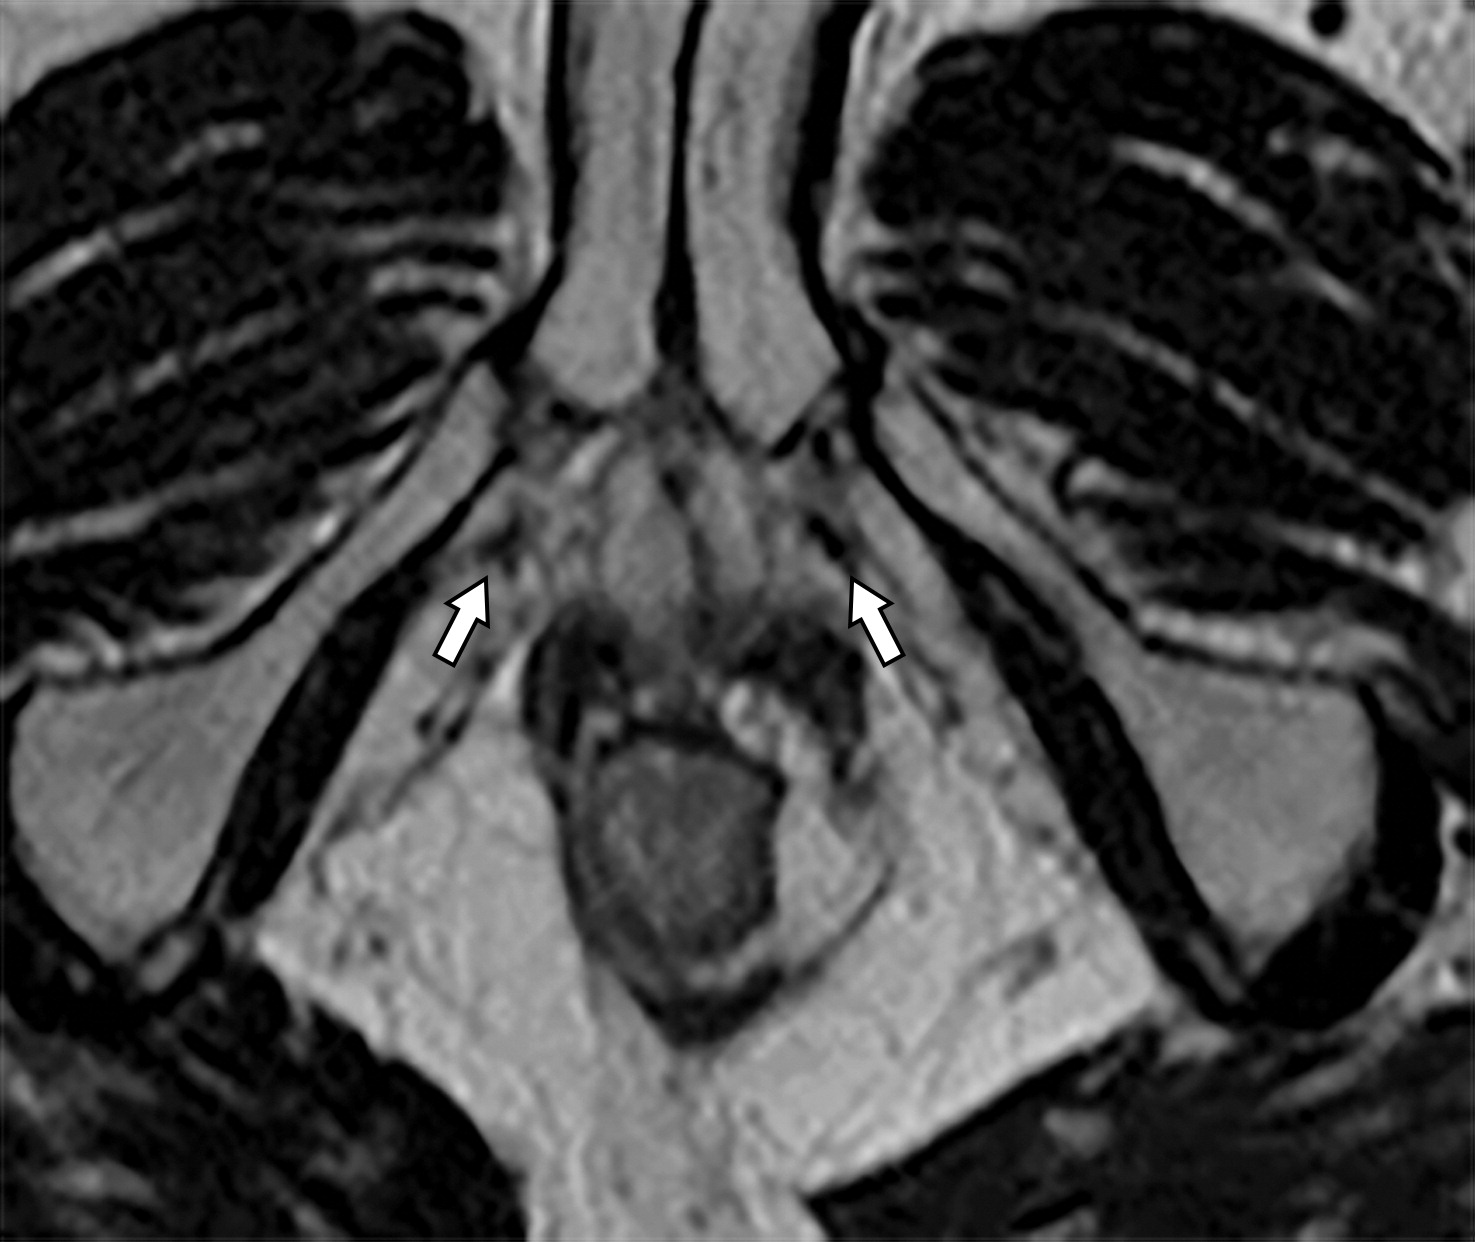

50岁以上男性骨盆和盆底的MRI解剖。

提肛肌(LA),由耻骨直肠肌(PR)、耻骨尾骨肌(PC)和髂尾骨肌(IC)组成;尾骨肌(C),前列腺(P),闭孔内肌(OI),会阴浅横肌(STP),球海绵体肌 (B), 坐骨海绵体肌(ISC),肛门外括约肌(EAS),肛门内括约肌(IAS),直肠(R),尿道括约肌(SU),也称为尿道外括约肌(U),它包围着整个膜性尿道。6774449af17bb1b8df6e83ab4e9fa158.jpeg